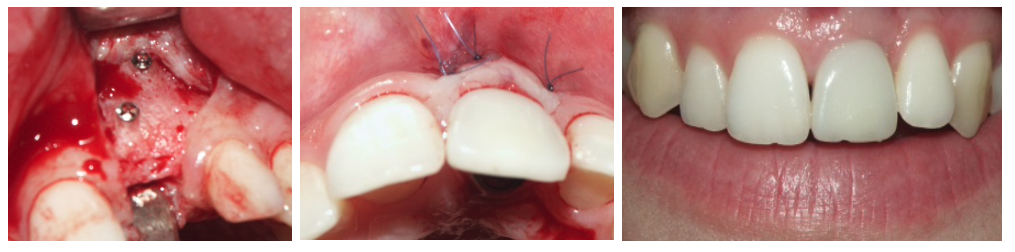

Paciente con fracaso periodontal de los 4 dientes anteriores. El mismo día se le realizaron las exodoncias de los4 dientes, se le colocaron 2 implantes y sobre ellos los dientes fijos provisionales (carga inmediata). Los dientes definitivos se confeccionaron en metal-cerámica.

Foto de la toma de modelos de los dientes fijos provisionales, y de los mismos, confeccionados el mismo día de la cirugía.

Paciente con fracaso del diente 22 cuyo tratamiento ha sido exodoncia, implante inmediato y carga inmediata (diente fijo provisional en el día (Foto inferior)) e injerto de conectivo. Corona definitiva de cerámica.

Rehabilitación del diente 21 con carga inmediata

Paciente con fractura de la raíz del diente 21. El caso se resolvió mediante exodoncia, implante inmediato y carga inmediata (diente fijo provisional en el día) e injerto de conectivo. La corona definitiva se confeccionó en metal cerámica .

Imagen de la toma de modelos de los provisionales en día de la cirugía de colocación del implante, y de la rx apical con el diente fijo provisional puesto